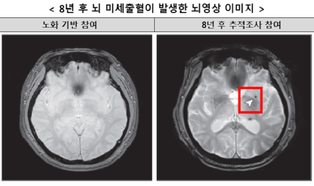

- 수면무호흡증, 뇌 미세출혈 위험 2배 증가시킨다